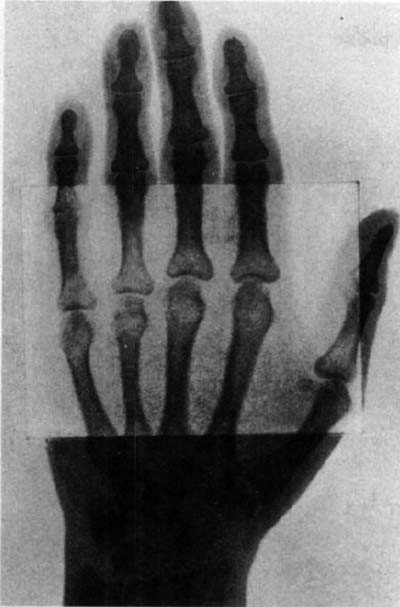

図6.増感紙をフィルムの一部に重ねてその効果を示したもの「濃度の高い被写体の撮影において露光時間を大きく短縮して撮影者にとってきわめて大きな力となる.骨格系で特に有用である」と付記されている[6].

写真乾板のX線に対する感度が可視光よりも小さいことから,蛍光物質を塗布した増感紙(screen)を併用して感度を増大しようとする考え方は初期からあった(図6).1896年2月,アメリカ,コロンビア大学の物理学者Michael Pupinは,手の散弾銃創の患者の撮影を試みたが痛みのために長時間の撮影に耐えられず失敗した.しかし手元にあった友人Thomas Edisonから入手したタングステン酸カルシウムの蛍光スクリーンで透視したところ銃弾が明瞭に見えたので,写真乾板に蛍光板を重ねて再度撮影を試みたところわずか数秒で成功したという[4].